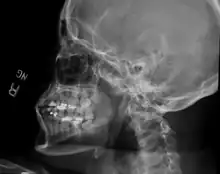

As with other joint dislocations, clinical history and examination are important for diagnosis. Commonly, plain and panoramic X-rays are used to determine the relative position of the mandibular condyle. If a complex or unusual injury is suspected, computed tomography is most reliable in diagnosing dislocation and possibly associated fractures or soft tissue injuries.

-

Bilateral anterior dislocation of the jaw -

Jaw dislocation following relocation -

CT image demonstrating jaw dislocation